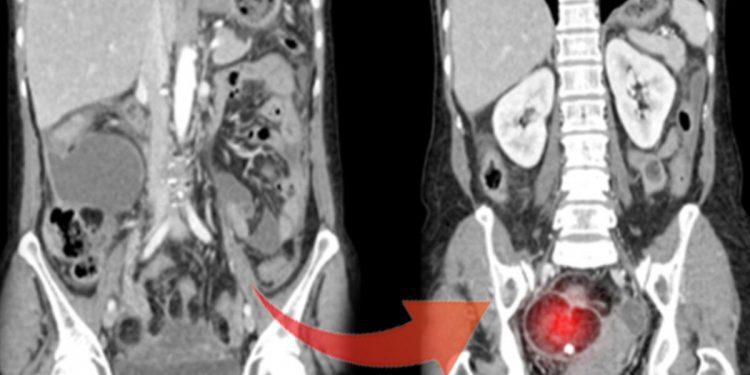

Form 1-Dermoid kistli yumurtalık Biçim 2-Normal yumurtalık